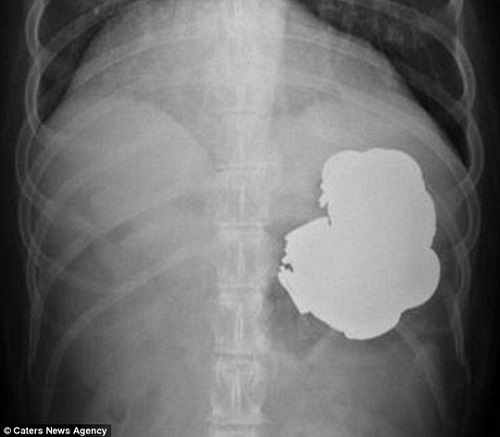

Dị vật kim loại trong cơ thể bệnh nhân

Tuy nhiên, kết quả nội soi và X- quang khiến bác sĩ hết sức kinh ngạc: Người đàn ông đã nuốt hàng trăm đồng tiền xu, đinh vít và móng tay. Theo lời bệnh nhân, trong khoảng 3 năm, Rajpal Singh đã nuốt tổng cộng 140 đồng xu, 150 đinh vít cùng các loại hạt, bu lông, móng tay, pin, nam châm…

Ngay sau đó, các bác sĩ đã phẫu thuật nội soi trong 9 giờ để gắp 240 vật lạ từ dạ dày người đàn ông.